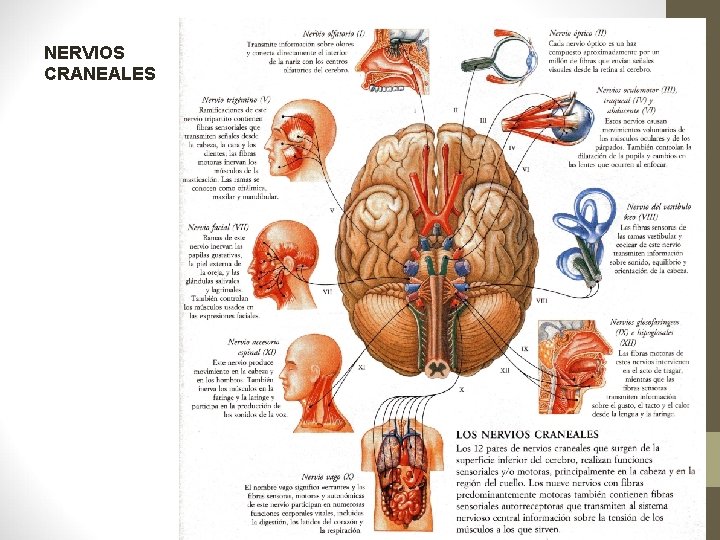

NERVIOS CRANEALES

NERVIOS CRANEALES NERVIO I. Olfatorio TIPO FUNCIÓN Sensorial Olfato II. Óptico Sensorial Visión III. Oculomotor Motor Eleva párpado superior; gira globo ocular hacia arriba, abajo y adentro; contrae pupila; acomoda al ojo IV. Troclear Motor Ayuda a girar el globo ocular hacia abajo y afuera V. Trigémico 1 -Rama oftálmica 2 -Rama maxilar 3 -Rama mandibular Mixto 1. Córnea, piel de la frente, cuero cabelludo, párpados y naríz; mucosa nasal 2. Piel de la cara sobre maxilares; dientes del maxilar; paladar; mucosa de la naríz 3. Músculos masticación, tensor del velo del paladar; tensor del tímpano. Piel de la mejilla; piel sobre mandíbula y costado de la cabeza; dientes de mandíbula; articulación temporo-mandibular; mucosa de la boca y parte anterior de la lengua

NERVIOS CRANEALES NERVIO TIPO FUNCIÓN VI. Abducente Motor Músculo recto lateral gira globo ocular lateralmente VII. Facial Mixto Músculos del rostro y cuero cabelludo; gusto de 2/3 anterior de la lengua; piso de la boca y paladar; glándulas salivales submandibulares y sublinguales; glándulas lacrimales, naríz y paladar VIII. Vestibulococlear Sensitivo 1. Vestíbulo 2. Coclear 1. Utrículo, sáculo y conductos semicirculares: posición y movimiento de la cabeza 2. Órgano de Corti: audición. IX. Glosofaríngeo Mixto Deglución; glándula parótida; sensibilidad general y gustativa del tercio posterior de lengua y faringe X. Vago Mixto Corazón y grandes vasos toráxicos; laringe, tráquea, bronquios y pulmones; tubo digestivo entre faringe y ángulo del colon; hígado; riñones; páncreas

NERVIOS CRANEALES NERVIO TIPO FUNCIÓN XI. Accesorio 1. Raíz craneal 2. Raíz espinal Motor 1. Músculos del paladar blando, de la faringe y de la laringe 2. Músculos esternocleidomastoídeo y trapecio XII. Hipogloso Motor Músculos de la lengua (excepto el palatogloso) que controlan su forma y movimiento